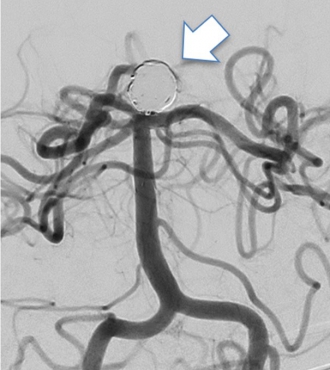

破裂によりくも膜下出血の原因になるものですが、カテーテルを脳動脈瘤内に誘導しコイルという金属を瘤内に留置することで破裂の予防をします。動脈瘤の描出を無くすことで破裂の予防が可能です(下図)。

手技を確実にするため、ステントというメッシュ状の筒を補助で使用することがあります。

治療前

治療後